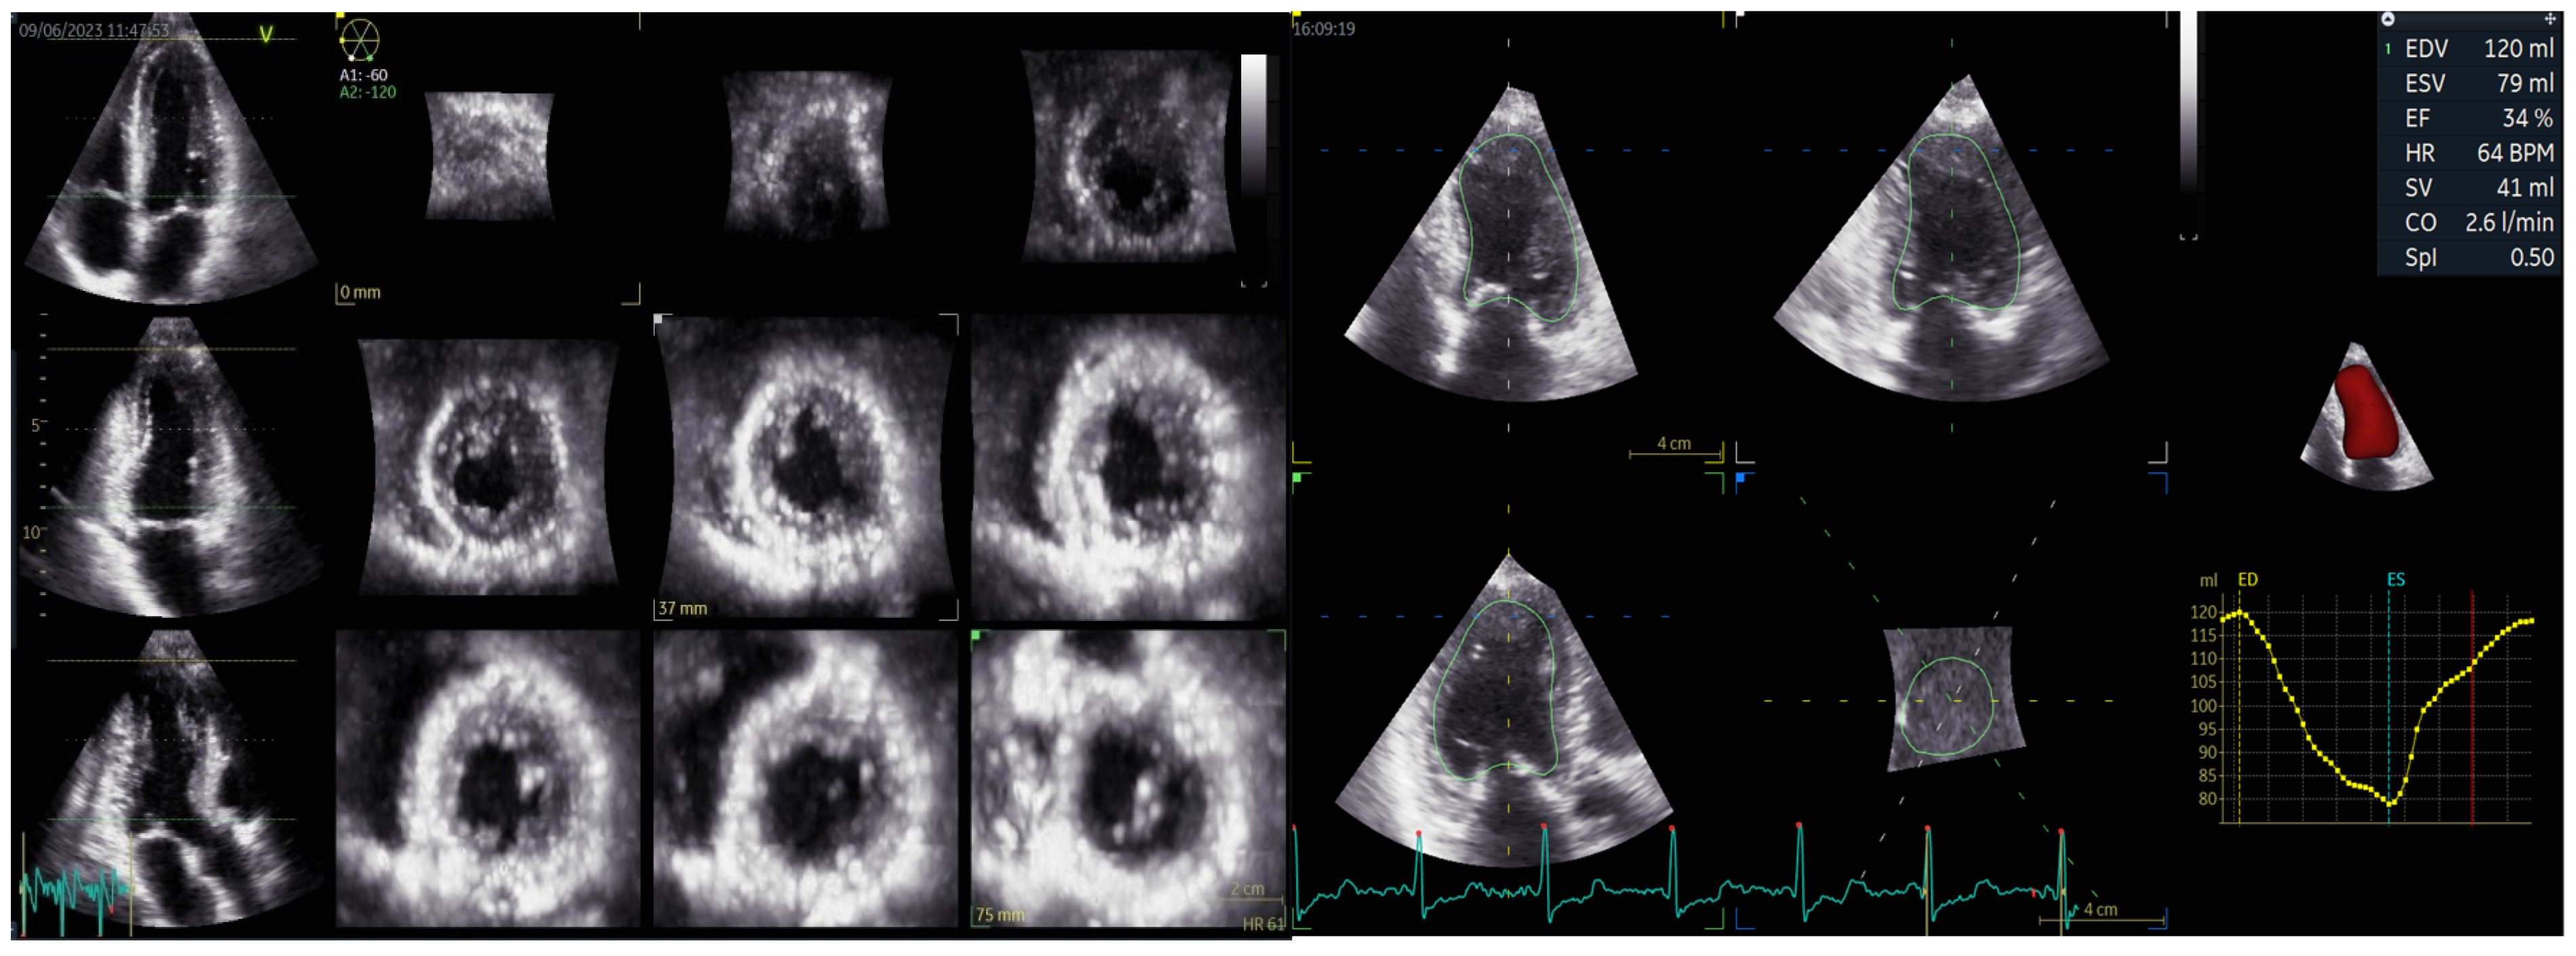

| 3D LVEDV (mL/mp) | 52.3 ± 11.3 | 57.1 ± 13.89 | 68.29 ± 13.14 | 55.22 ± 13.14 | 0.002 |

| 3D LVESV (mL/mp) | 22.9 ± 7.2 | 32.91 ± 11.01 | 46.28 ± 12.49 | 30.65 ± 9.03 | 0.001 |

| 3D LVEF (%) | 40.14 ± 14.71 | 43.17 ± 7.74 | 37.16 ± 6.307 | 44.88 ± 6.605 | <0.0001 |

| 3D SV (mL) | 56.07 ± 5.54 | 46.54 ± 10.16 | 40.22 ± 7.57 | 48.55 ± 9.55 | 0.013 |